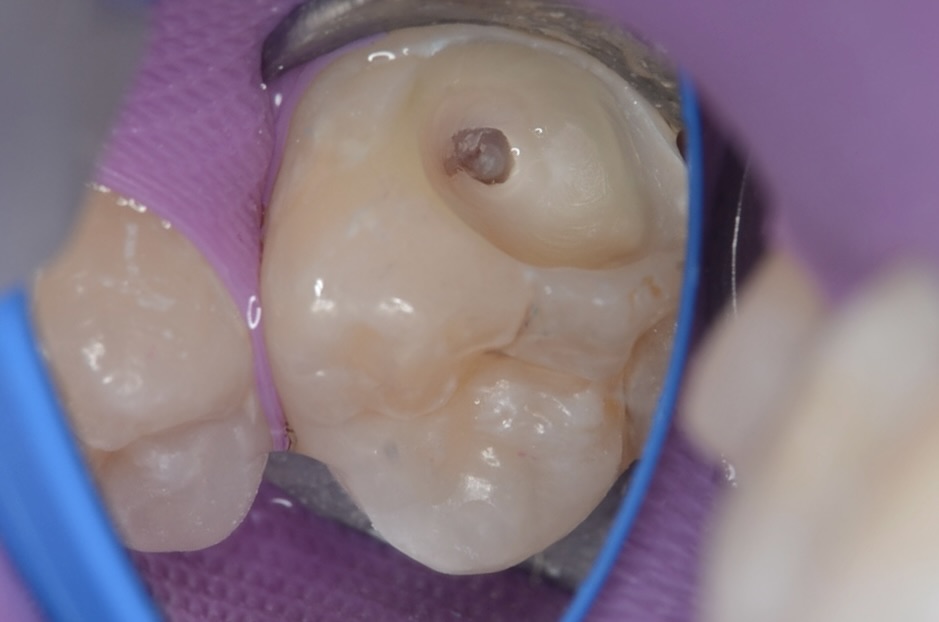

まだ染まる虫歯

丁寧に虫歯を取り除きます。 -

露髄

完全に虫歯をとると神経が露出しました。 -